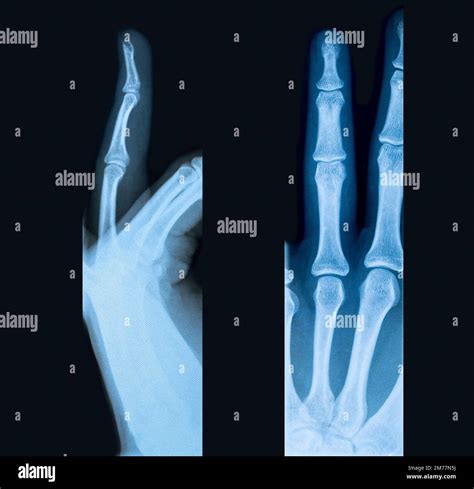

Ignoring fractured finger symptoms is never a recommended strategy. If you suspect you have broken a finger, it is essential to consult with a healthcare professional, such as a primary care doctor, an urgent care specialist, or an orthopedic hand surgeon. Even if the break seems minor, a doctor can confirm the diagnosis through a physical examination and imaging tests, usually X-rays.

Imaging is crucial because it allows the doctor to see the exact location and nature of the fracture. A hairline fracture might not show the obvious deformity of a complete break but can still cause significant issues if not properly splinted. Furthermore, identifying the specific type of break—whether it is stable, unstable, or intra-articular (extending into the joint)—is vital for determining the appropriate treatment plan, which could range from simple splinting to surgical intervention.